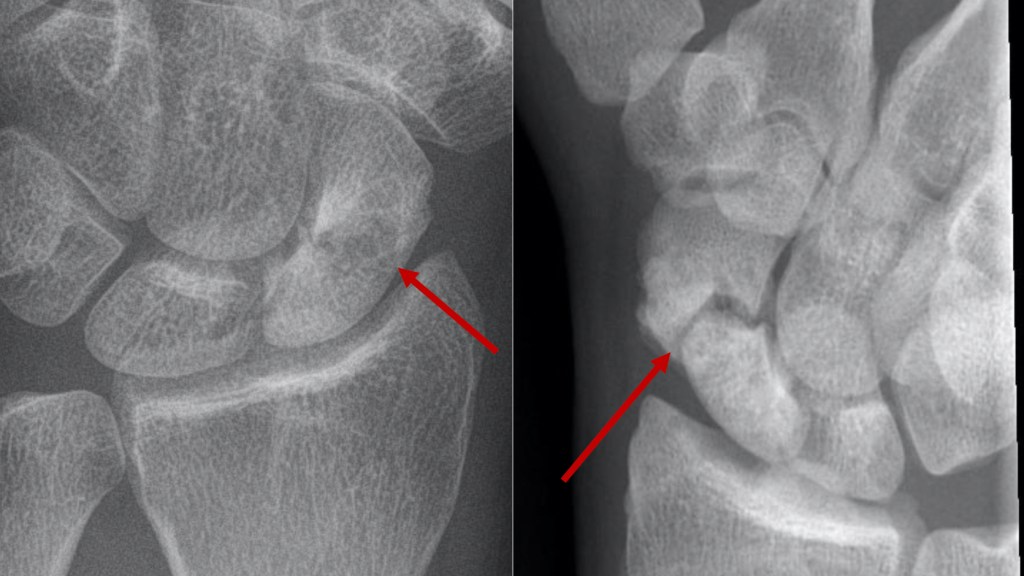

Surgery – Where symptoms are causing a problem, surgery is usually recommended. The operation involves taking a piece of bone from either the pelvis or the forearm (from a place where it will not be missed!) and placing it between the ends of the scaphoid bone. Sometimes a vascularised bone graft (a piece of bone with a small blood supply) may be suggested. For some cases, this type of bone graft may aid healing. The bone is then ‘fixed’ with a screw which holds everything in place until the bone heals. The screw is placed inside the bone, and usually stays there forever.